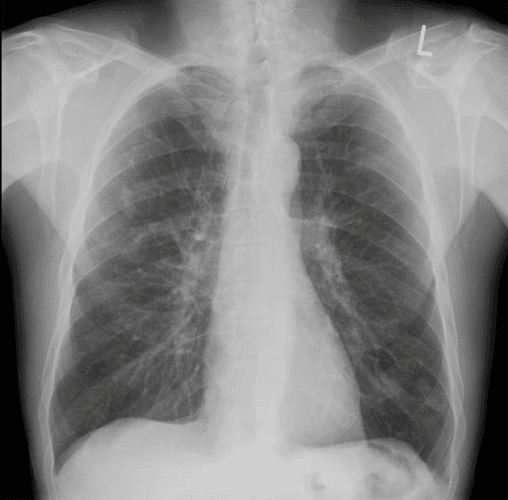

45 year old was transferred from a peripheral facility for acute massive hemoptysis though maintained sufficient airway patency with no evidence of hemodynamic instability or respiratory failure.  Thoracic auscultation revealed vesicular breathing with no adventitious sound.  CXR from the peripheral site was normal (see Figures 1 & S1).

Figure 1. Chest X-ray appears normal.

Figure S1. Chest x-ray appears normal. Related to Figure 1.

Multiple studies have demonstrated the superiority of thoracic PoCUS in identifying interstitial syndrome compared to conventional chest x-ray.   In this particular case, the CXR was essentially normal though PoCUS demonstrated otherwise.